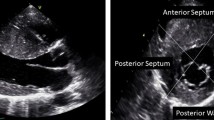

While asymmetric hypertrophy (a septal-to-posterior wall thickness ratio ≥ 1.3 in normotensive patients or ≥ 1.5 in hypertensive patients) may be suggestive of HCM, it is not a specific finding (Fig. 1). Thus, about 10% of patients with hypertension (HTN) have asymmetric hypertrophy, and right ventricular (RV) hypertrophy can also lead to septal thickening [19]. Moreover, misalignment of the transducer beam can lead to oblique sections with wall thickness (WT) overestimation, while inclusion of RV structures (e.g., moderator band, trabeculations) when measuring the septum can also lead to a wrong HCM diagnosis [19]. The interventricular septum (IVS) morphology can also offer information about the presence of sarcomeric gene mutations. A reverse IVS curvature is associated with a high probability of disease-associated allele, while patients with a sigmoid IVS are much less likely to have a positive genetic test [20].

Complex mechanisms leading to dynamic obstruction in a patient with HCM. Concentric hypertrophy involving mainly the basal septum (diastolic IVS thickness of 15 mm), and elongated mitral leaflets with systolic anterior motion (a); M-mode echocardiography shows the systolic contact of the mitral valve with the IVS (arrows) (b); anterior displacement of the hypertrophied papillary muscles (c, d); moderate eccentric (posteriorly oriented) mitral regurgitation secondary to SAM (e); and significant resting LVOT obstruction by CW Doppler (peak resting gradient of 102 mmHg) (f). Of note, there is severe LVOT obstruction without severe septal hypertrophy, explained by the significant abnormalities of the mitral valve apparatus. HCM hypertrophic cardiomyopathy, IVS interventricular septum, LVOT left ventricular outflow tract